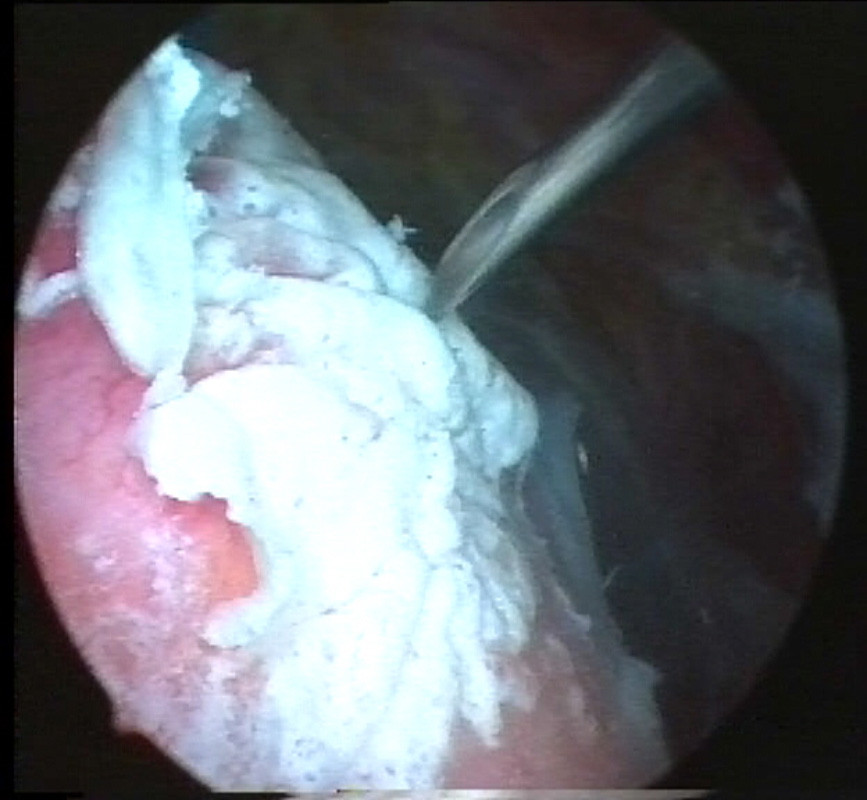

Der in der Sehne gelegene Kalkherd wird mit einer Hohlnadel (Bild 2) (der Kalk bleibt in der Nadelöffnung hängen) lokalisiert, danach wird der Kalk nach Eröffnung der betroffenen Sehne mit einem Löffel (Bild 3) möglichst vollständig entfernt und abgesaugt.